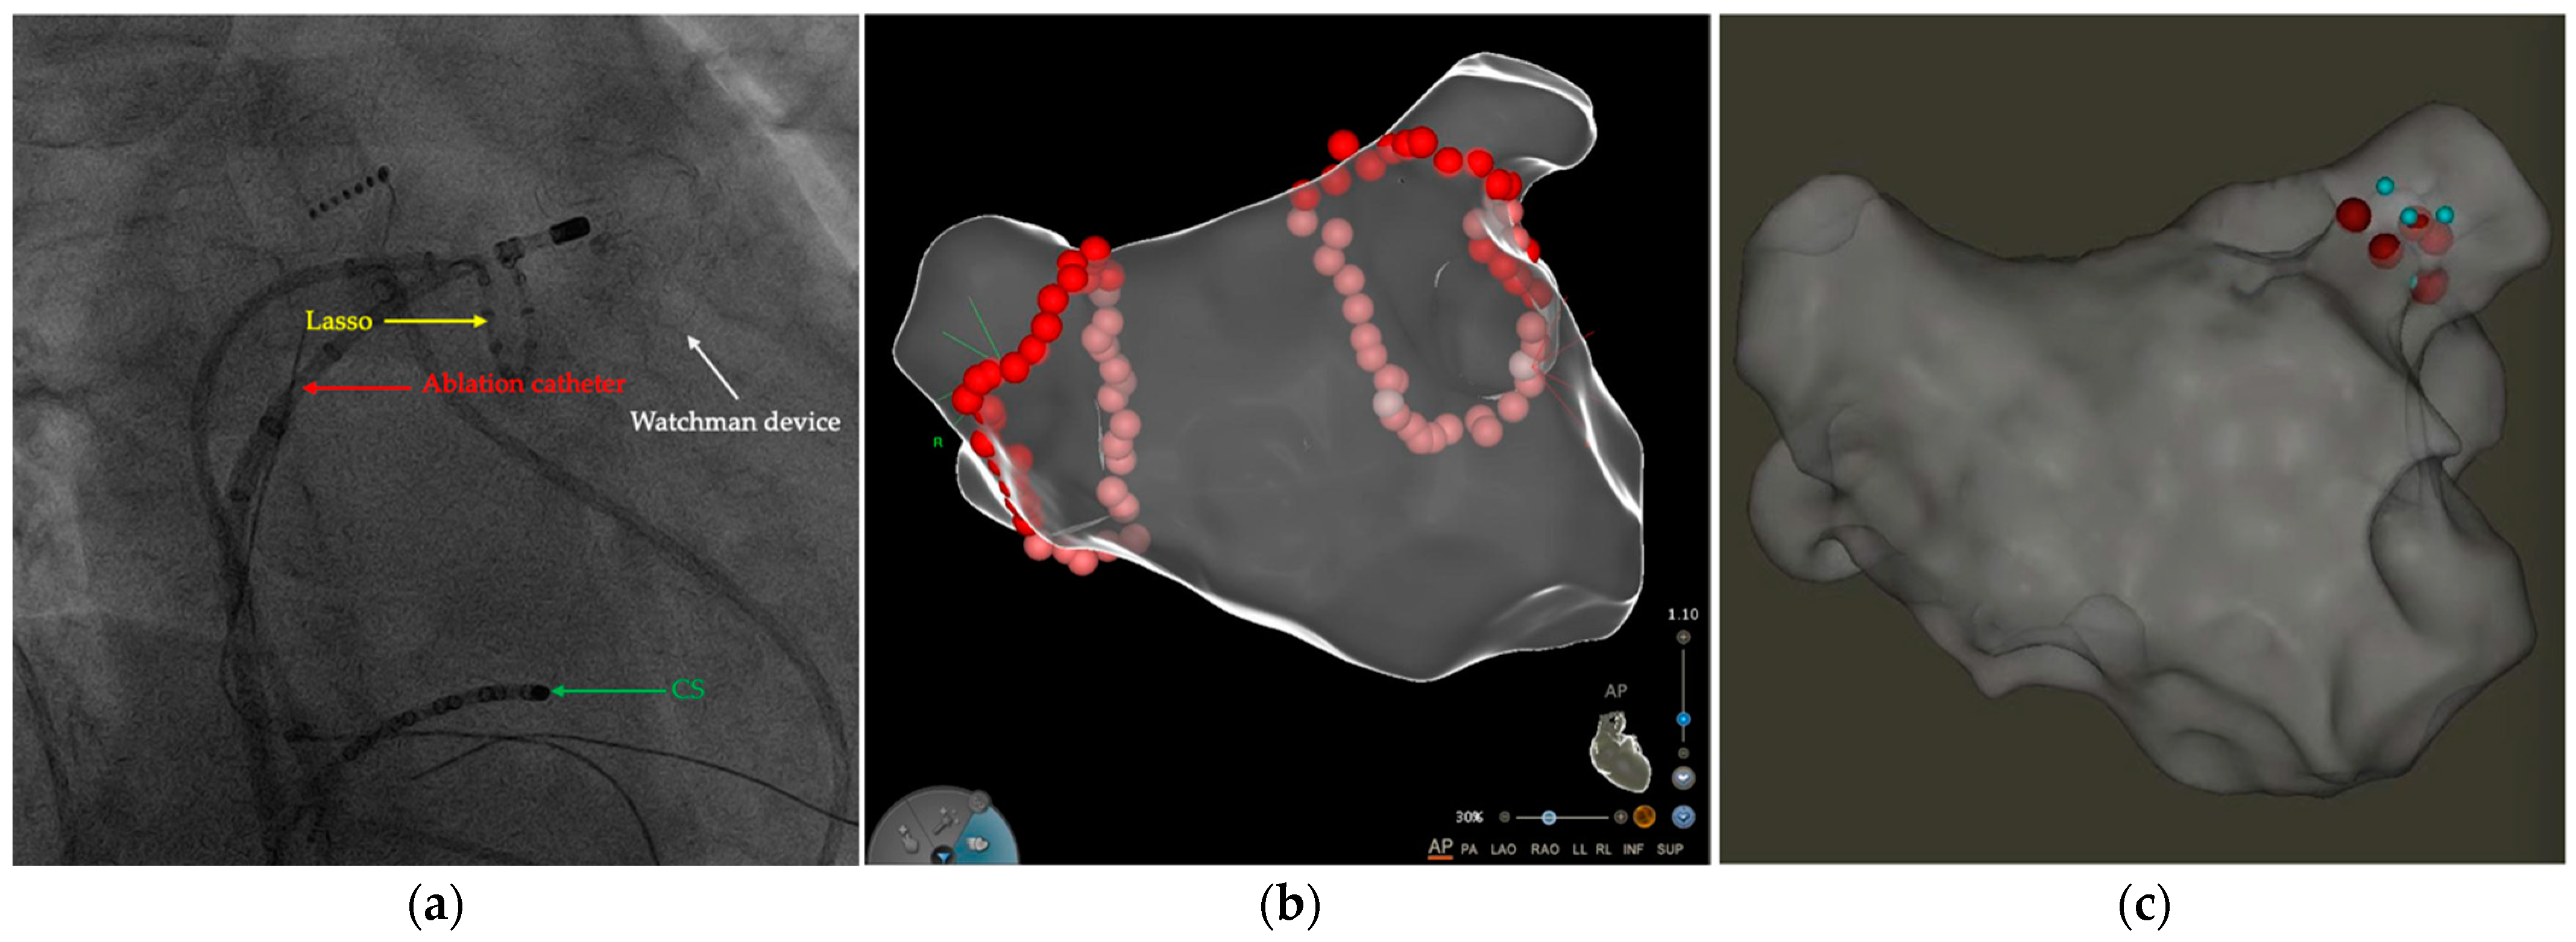

2.2. LA CA Procedure

3.2. Periprocedural Data